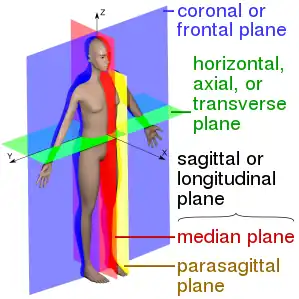

The main anatomical planes of the human body, including sagittal or median (red), parasagittal (yellow), frontal or coronal plane (blue) and transverse or axial plane (green) | |

The coronal plane is an example of a longitudinal plane. For a human, the mid-coronal plane would transect a standing body into two halves (front and back, or anterior and posterior) in an imaginary line that cuts through both shoulders. The description of the coronal plane applies to most animals as well as humans even though humans walk upright and the various planes are usually shown in the vertical orientation.